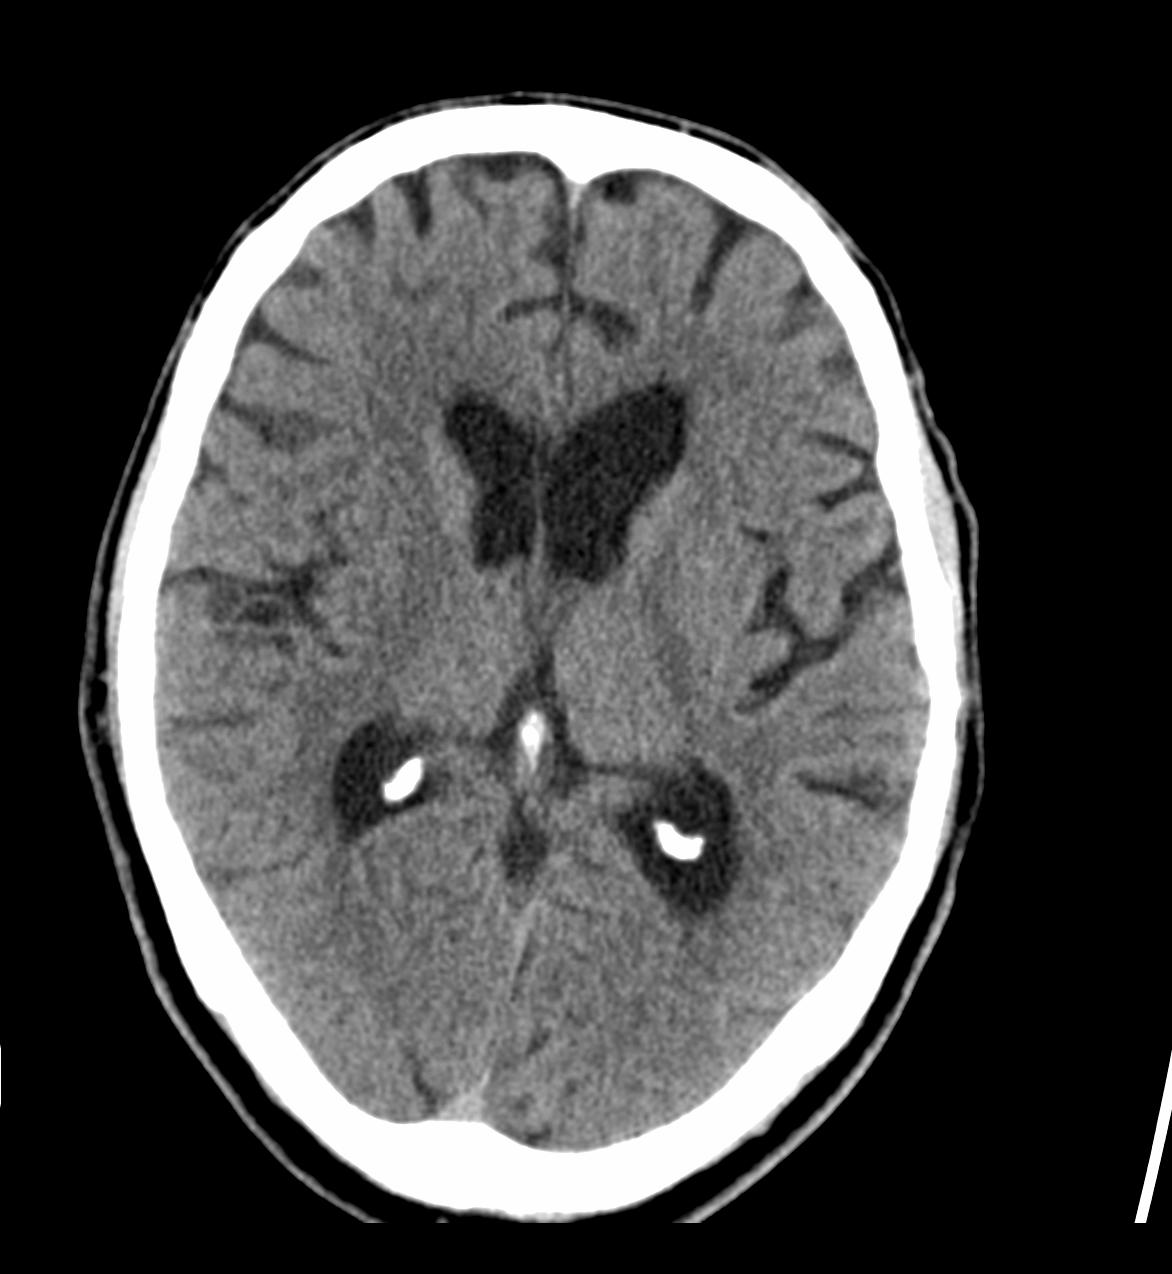

(Darstellung des Hirnschädels, Mittelgesicht, Nasennebenhöhlen und Felsenbeine)

Bei diesen Untersuchungen ist keine spezielle Vorbereitung notwendig. Je nach Fragestellung kann die intravenöse Gabe von Kontrastmittel erforderlich werden.

Die Untersuchungsdauer ohne Kontrastmittelgabe beträgt ca. 10 Minuten, mit Kontrastmittelgabe ca. 20 Minuten.